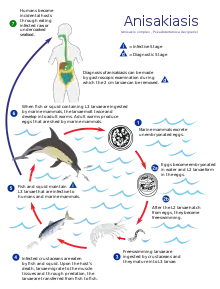

There are three main kinds of parasites: Clonorchis sinensis (a trematode/fluke), Anisakis (a nematode/roundworm) and Diphyllobothrium (a cestode/tapeworm). Infection by the fish tapeworm Diphyllobothrium latum is seen in countries where people eat raw or undercooked fish, such as some countries in Asia, Eastern Europe, Scandinavia, Africa, and North and South America.[71] Infection risk of anisakis is particularly higher in fishes which may live in a river such as salmon (shake) in Salmonidae, mackerel (saba). Such parasite infections can generally be avoided by boiling, burning, preserving in salt or vinegar, or freezing overnight. Even Japanese people never eat raw salmon or ikura (salmon roe), and even if they seem raw, these foods are not raw but are frozen overnight to prevent infections from parasites, particularly anisakis.

Below are some life cycles of fish parasites that can infect humans:

Life cycle of the liver fluke Clonorchis sinensis Life cycle of the parasitic Anisakis worm

Life cycle of the parasitic Anisakis worm Life cycle of the fish tapeworm Diphyllobothrium latum